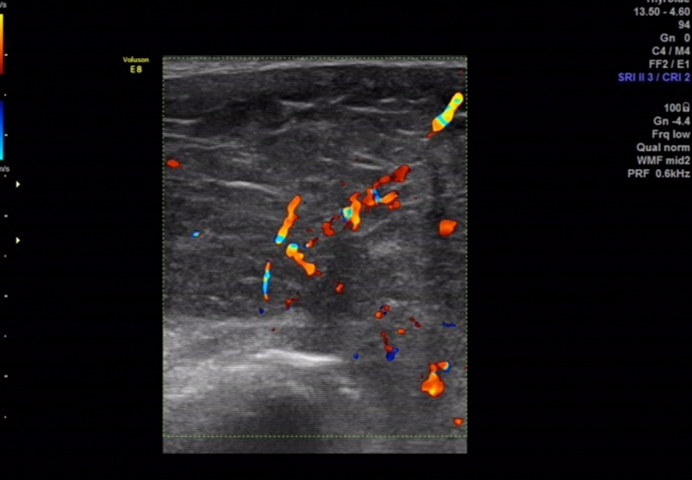

超声所见

骶尾部皮下软组织层内探及一范围约 145×98×107mm 的低回声包块,围绕骶骨生长,部分向盆腔内生长,与周围其他组织分界清楚,内部回声欠均匀, CDFI:内见多个条状血流信号, PW 检测:呈动脉频谱, RI:0.72 。

图 4 PW检测呈动脉频谱, RI:0.72

图 5 用线阵探头经骶尾部扫查:内部回声欠均匀,见多个条索状高回声,可见多个条状血流信号